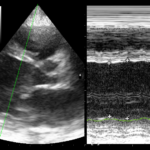

This book teaches you the basics of ultrasound and extends to more advanced techniques.

We cover a wide range of US topics including Physics, Cardiac, Thoracic, Abdominal, Vascular, Neurological, Early Pregnancy and Gynaecology, Soft Tissue and MSK, ‘Hospital at Home’, Prehospital, Military, Remote Medicine, COVID-19 and more…!

Focused Intensive Care Echocardiography (FICE)

Point of care ultrasound (POCUS) is being increasingly utilised within acute and critical care environments as an adjunct to the clinical assessment of acutely unwell